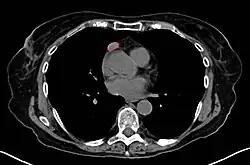

Work-Up

• CT scan

• Thymoma typically presents in the anterior/superior mediastinum